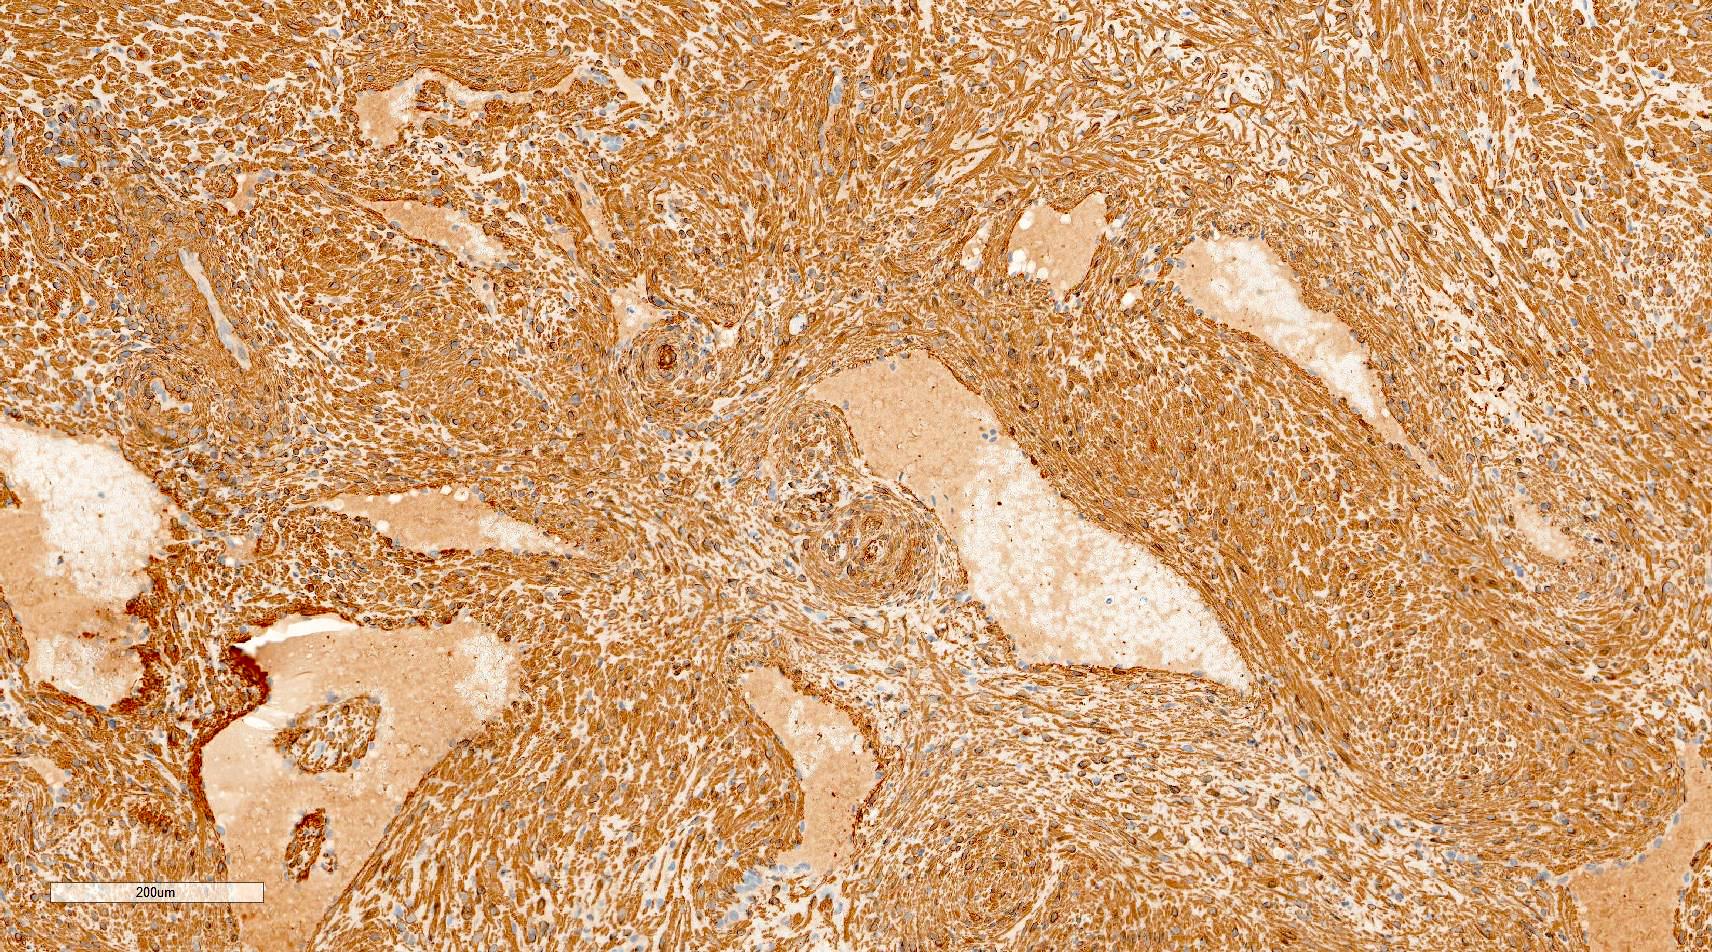

Microscopic (histologic) images

Contributed by Ohoud Aljarbou, M.D., Jijgee Munkhdelger, M.D., Ph.D. and Andrey Bychkov, M.D., Ph.D.

Positive stains

- Actins (alpha smooth muscle actin and HHF35) and calponin (diffuse positivity) and diffusely or focally positive for h-caldesmon

- Desmin has variable positivity, observed in 75% of solid type, 50% of the venous type and only 18% of the cavernous type (Hum Pathol 2007;38:645)